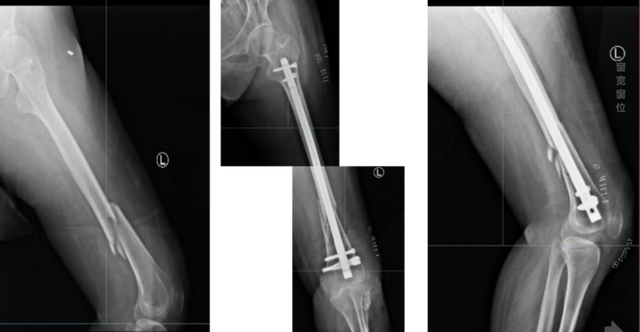

股骨粗隆间伴粗隆下骨折PFNA髓内钉内固定

肱骨骨折髓内钉内固定

股骨干骨折顺行髓内钉内固定术

股骨干中远段骨折逆行髓内钉固定